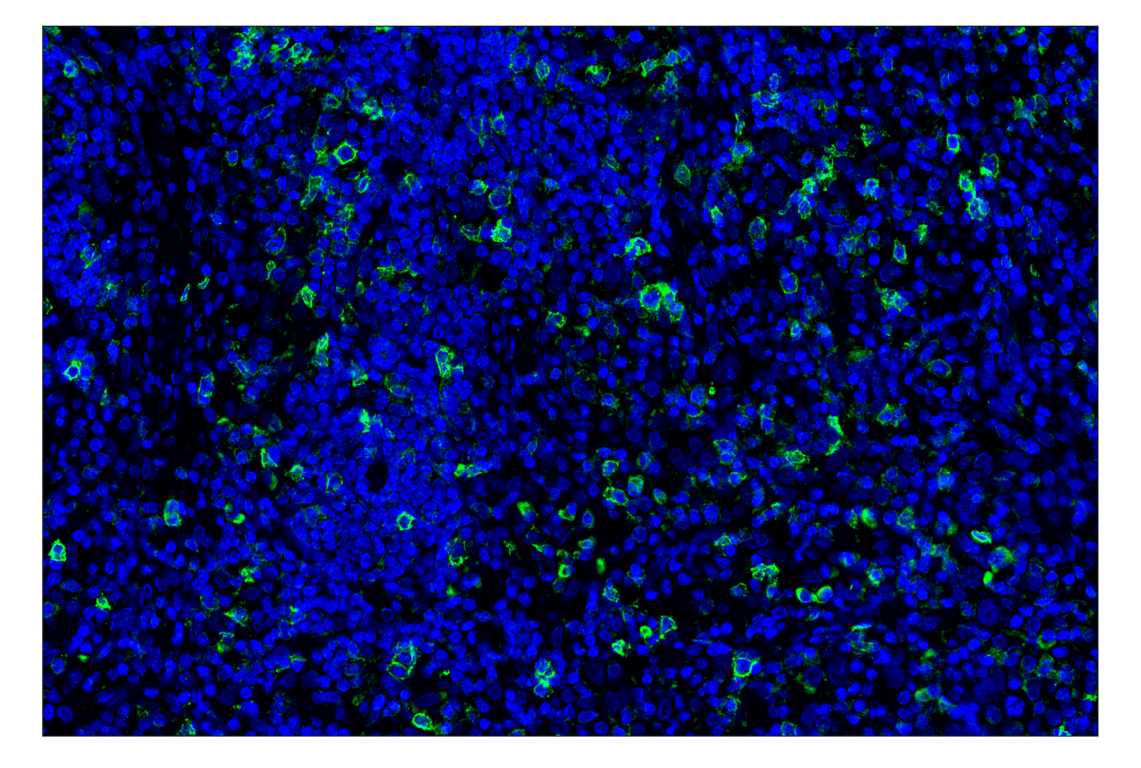

ICOS (D1K2T) Rabbit Monoclonal Antibody (Alexa Fluor® 488 Conjugate) #35988

Immunohistochemistry (Paraffin) 1:50 - 1:200

ICOS (D1K2T) Rabbit Monoclonal Antibody (Alexa Fluor® 488 Conjugate) detects endogenous levels of total ICOS protein.

Species Reactivity:

Human, Monkey